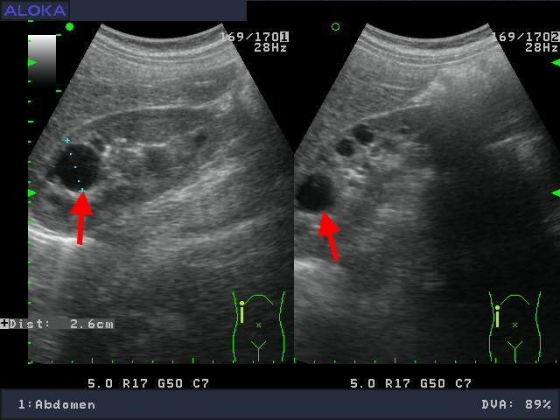

醫學影像..腹部超音波 :膽囊

膽囊腫瘤

膽結石